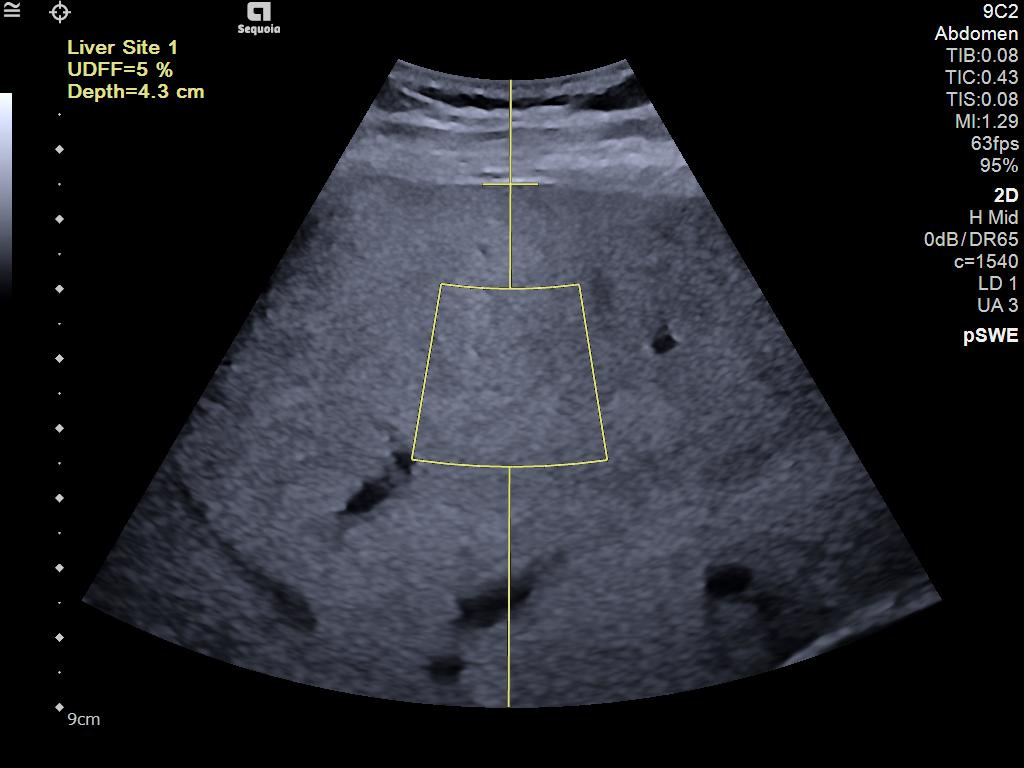

- AI Abdomen automatically recognizes and labels 17 anatomical views and 12 routine measurements.

- Ultrasound Derived Fat Fraction (UDFF) for quantitative ultrasound for liver disease assessment.

- Auto pSWE to reduce liver elastography exam time by up to 75%*.